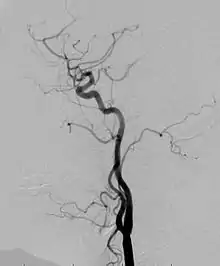

PWS can be distinguished from other conditions because of its defining port-wine stains that are large, flat and pink. The port-wine stains and physical examination are enough to diagnose PWS.[22] But additional testing is necessary to determine the extent of the PWS syndrome. The following tests may be ordered by physicians to help determine the appropriate next steps: MRI, ultrasound, CT/CAT scan, angiogram, and echocardiogram.[22]

Angiogram: an angiogram can also be ordered to get a detailed look at the blood vessels in the affected or overgrown limb. In this test a physician injects a dye into the blood vessels that will help see how the blood vessels are malformed.[22]